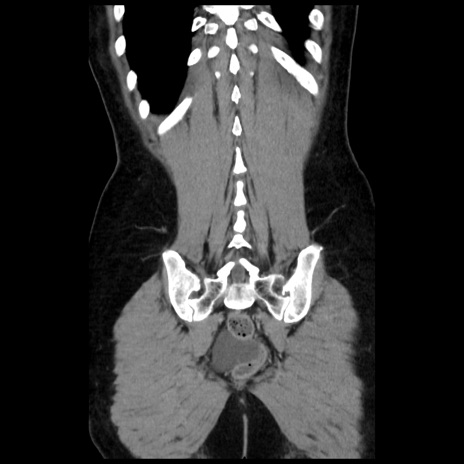

症例10(冠状断像)

【症例】 50歳代女性

【主訴】 腹痛

【現病歴】前日生レバーを食べた。今朝に排便あり。 昼前に突然発症の腹痛を生じ、当院救急外来を受診した。

【既往歴】 子宮筋腫にてで子宮全摘後

【身体所見】 意識清明、腹部:平坦、軟、下腹部やや左を中心に圧痛・反跳痛あり、筋性防御あり

【データ】WBC 7800、CRP 0.07